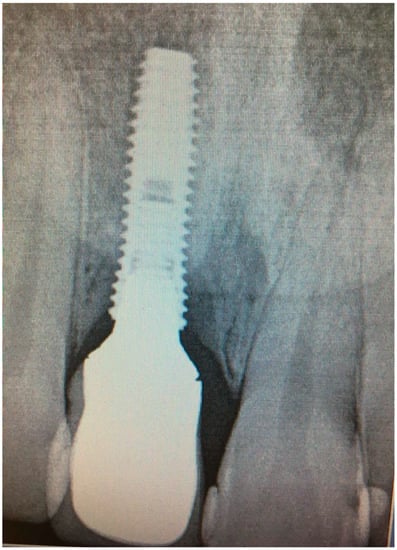

Bidimensional radiographic assessment of the lower jaw implants (with periapical and panoramic radiograph) was done. In the lower jaw, a concave bone resorption of about 2.5 mm mesial and distal to both distal implants were observed, and there was no bone resorption in two central implants (Figure 13 and Figure 14).

Figure 13.

X-ray of 3.5 dental implant in patient in 6 months after treatment.

In 1 year the clinical assessment allowed to find a probing depth of 1.5–3 mm mesial/circumferentially without bleeding in the two lower jaw distal implants and a probing depth of 0.5–1 mm mesial/circumferentially without bleeding in the two lower jaw central implants (Figure 12).